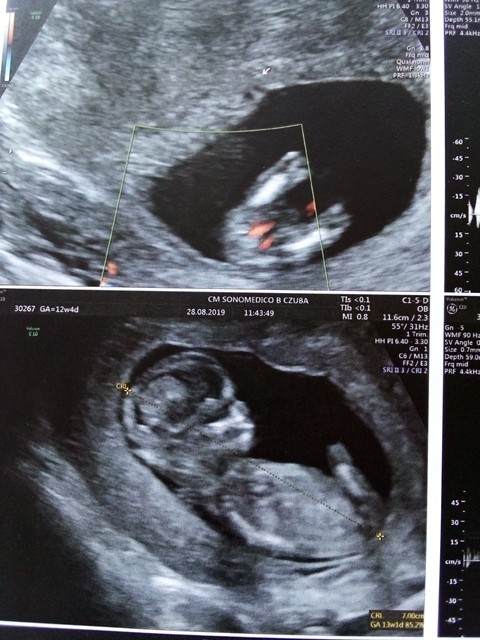

Hey dziewczyny .USG 12 tydzień ciąży.Widzicie tu chłopca czy dziewczynkę ? Zerknijcie proszę ...

Załączniki

• 115804223_339958607398878_5640781852298220012_n.jpg

115804223_339958607398878_5640781852298220012_n.jpg

162,2 KB · Wyświetleń: 368